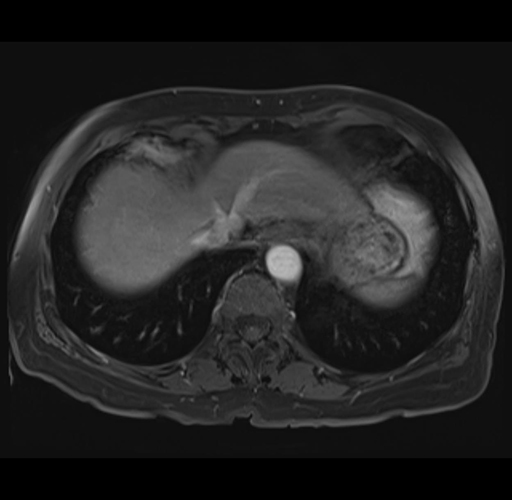

Imaging Analysis

Look through the patient's CT scan to identify any areas of concern for the necessary procedure.

MRI T1

Based on your CT findings, which issue(s) would give reason for "planned slowing down moment(s)" in this case?

Considering a standard right hepatectomy procedure, what step(s) of the operation would you do differently in this case?